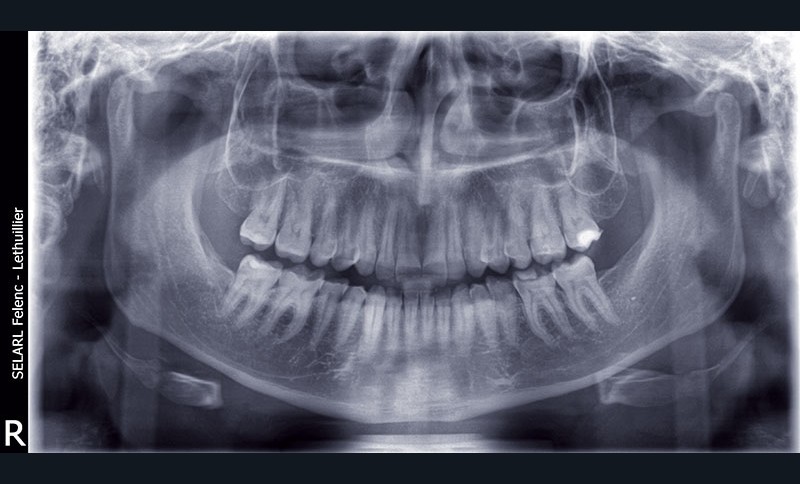

L’examen radiologique ne révèle aucune perte osseuse interproximale, ni de lésions endodontiques (fig. 8).